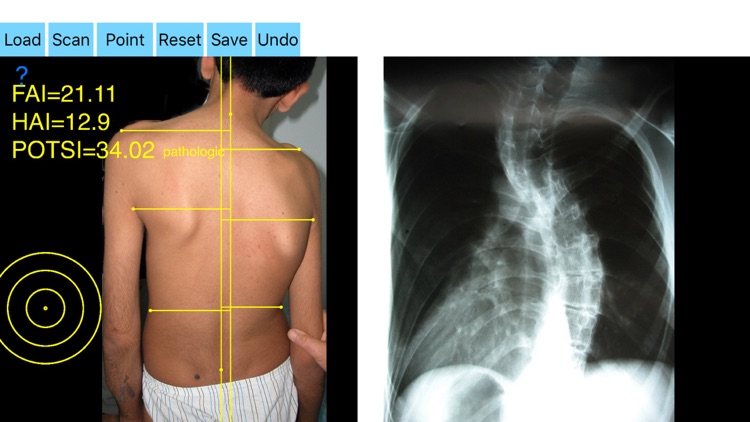

By visual inspection of the spine, asymmetry of the back is significant enough to suspect the existence of scoliosis in such cases, to evaluate spinal deformity an X-ray is ordered. Scoliometers could help evaluate the appearance of an asymmetric spine deformity with variable sensitivity and specificity but cannot substitute radiography. It is widely reported in the literature that significant correlations between radiographs and topographic parameters were found. Posterior Trunk Symmetry Index (POTSI) is a useful Index in the assessment of spinal deformity. POTSI Index is very sensitive in revealing any frontal plane asymmetry and could help identify moderate deformities which might otherwise be missed in clinics or physical examination. The Potsi Index is the sum two variables Height Asymmetry Index (HAI) and Frontal Asymmetry Index (FAI). Height asymmetry indexes are obtained as the sum of height differences of the shoulders, axillary folds, and waist creases, and it is normalized with the division of its value by the vertical distance from the C7 vertebra to the baseline of the gluteal cleft. The Potsi App calculates the Potsi Index according to the above mentioned developed topographic method (Suzuki N, Inami ) and offers a way to evaluate external back deformities with noninvasive technique. It is inexpensive and can be repeated indefinite times thus reducing unnecessary x-rays for normal anatomies and mild cases. The app helps the doctor in an outpatient setting to measure all the indexes in a blink of the eye by clicking few points.

-Securely import medical images directly from the camera or stored photos.

-by marking certain multiple anatomical points over the patients back the app can evaluate back’s symmetry in a few seconds. Eight specific points at the surface of the patient’s back are required. POTSI is relatively simple to measure, even on regular photography of the back. Ideal POTSI is zero, meaning full symmetry of the back surface. The App calculates all necessary elaborate formulas and after analysis the posterior trunk symmetry index(POTSI) is printed (normal value <10).